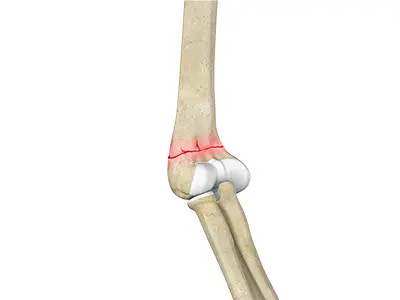

Distal Humerus Fractures of the Elbow

Injury in the distal humerus can cause impairment in the function of the elbow joint.

ORIF of the Distal Humerus Fractures

A distal humerus fracture is a condition that occurs when there is a break in the lower end of the humerus bone that commonly occurs as a result of severe trauma.